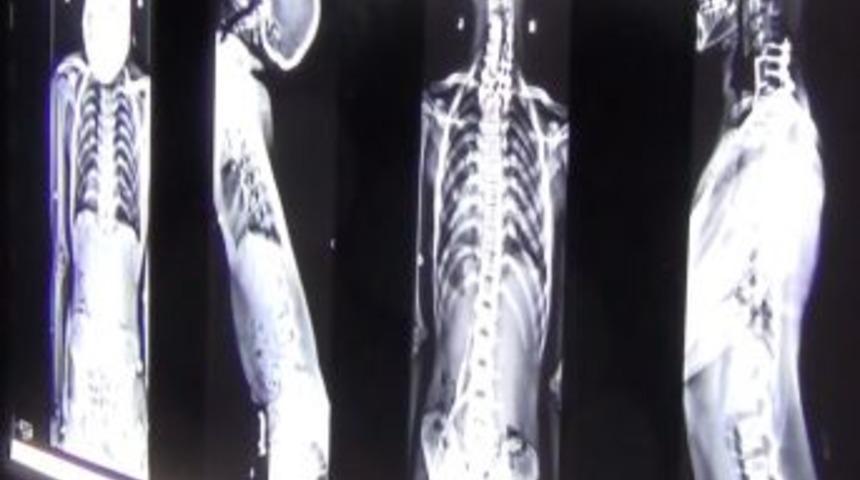

Boynunda ileri derecede geriye doğru büküklük şikayetiyle hastaların kendine ulaştığını kaydeden Köse, ikisi kardeş üç hastayı kendi geliştirdiği yöntemle tedavi etti. Onur ve Uğur Doğan kardeşler taburcu olurken, 16 yaşındaki Vedat Çevik’in tedavisi tamamlandı. Doç. Dr. Köse, ameliyat hakkında şu bilgileri verdi: "Hastalık sebebiyle kaslar iyice sertleşmiş, boyun geriye doğru ‘c’ şeklinde kıvrılmış ve öylece donmuş kalmış. Bu hastaları, yaklaşık 5 saat süren aynı anda üç aşamalı bir ameliyata aldık. Önce boynun ön tarafından girip C 7 boyun omurunu ve T 1 sırt omurunda kesiler yaptık. Sonra boynun arkasından yine kemik ve kas kesileriyle düzeltme ve gevşetme işlemi gerçekleştirdik. Yani kemik ve katılaşmış kaslarda kesitler oluşturarak boynu gevşettik, vidalarla sabitledik. Yeniden hastayı öne çevirip önden bir daha girip yeniden sabitledik. Boynun önden ve arkasından bir seansta üç ameliyat yapmış olduk. Artık karşıyı görmek için 70-80 derece eğilmeleri gerekmiyor. Normal bir insan gibi karşıya bakabiliyorlar."

Köse, yaptıkları araştırmada, böyle bir tedavi şeklinin tıp litaratüründe tanımlanmadığını, bu yöntemin dünyada ilk kez kendisi tarafından geliştirildiğini vurguladı. Ameliyatın, uluslararası tıp dergilerinde yayınlanması için hazırlık yaptıklarının kaydeden Köse, “Bu tedavi biçimi bu tür hastalara umut oldu. Karşıya bakabilmek için dik duramıyorlardı. 70-80 derece eğilip ancak karşı tarafa bakabiliyorlardı. Kas hastaları en azından artık daha konforlu biri hayat yaşayabilecekler.” diye konuştu.